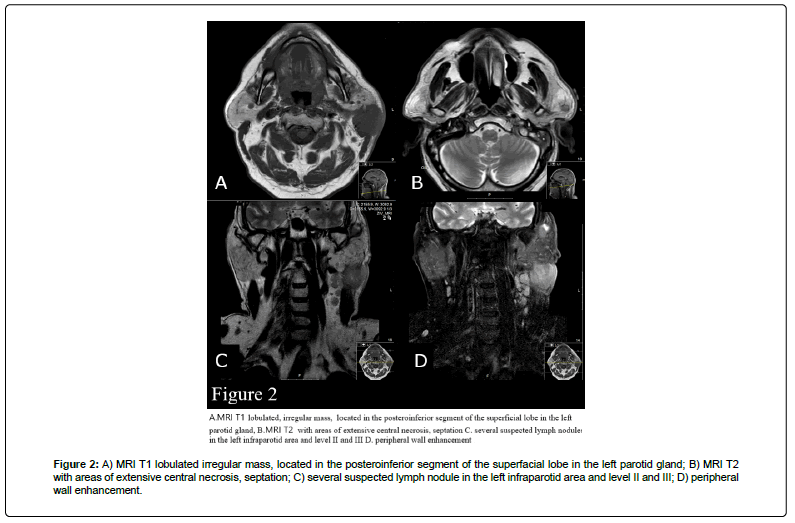

Contrast-enhanced Magnetic Resonance Imaging (MRI) revealed a lobulated, irregular mass, 37 mm × 39 mm × 47 mm located in the posteroinferior segment of the superficial and deep lobe in the left parotid gland, with areas of extensive central necrosis, septation, and peripheral wall enhancement contiguous with the anterior portion of external auditory canal and SCM muscle with subcutaneous tissue and skin involvement, several nodules in the left infraparotid area and level II were calcified (Figure 2).

Figure 2: A) MRI T1 lobulated irregular mass, located in the posteroinferior segment of the superfacial lobe in the left parotid gland; B) MRI T2 with areas of extensive central necrosis, septation; C) several suspected lymph nodule in the left infraparotid area and level II and III; D) peripheral wall enhancement.